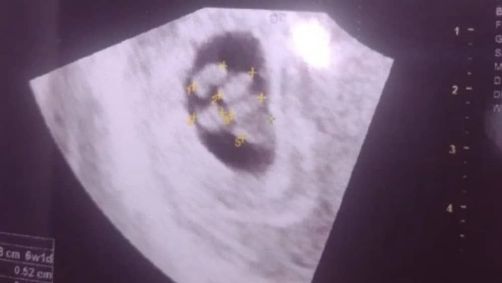

A gestação de quíntuplos é considerada um fenômeno raro. Estatísticas indicam que a chance de uma gravidez natural de quíntuplos é inferior a 1 em 55 milhões. O vídeo do ultrassom que revelou existência dos bebês viralizou nas redes sociais:

A mãe, Sara Silva, reagiu com surpresa à informação e passou mal ao descobrir a existência de mais de um bebe. O exame foi gravado pela mãe da Sara, Cláudia Campos, mas a surpresa foi tanta que o momento em que o médico fala do quinto filho não foi registrado.

Os bebês dividem a mesma placenta, ou seja, são irmãos idênticos. A gestação de quíntuplos exige cuidados médicos especiais e um planejamento minucioso para garantir a saúde da mãe e dos bebês. A possibilidade de um sexto bebê é ainda mais raro e aumenta o grau de complexidade da gravidez.